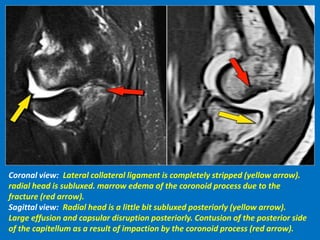

Coronal view: Lateral collateral ligament is completely stripped (yellow arrow).

radial head is subluxed. marrow edema of the coronoid process due to the

fracture (red arrow).

Sagittal view: Radial head is a little bit subluxed posteriorly (yellow arrow).

Large effusion and capsular disruption posteriorly. Contusion of the posterior side

of the capitellum as a result of impaction by the coronoid process (red arrow).